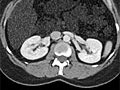

Una tomografía computarizada (CT, por sus siglas en inglés) utiliza rayos X para captar imágenes detalladas de estructuras del interior del cuerpo.

Una CT se puede usar para estudiar todas las partes del cuerpo, como el pecho, el abdomen, la pelvis o un brazo o una pierna. Puede tomar imágenes de los órganos del cuerpo, tales como el hígado, el páncreas, los intestinos, los riñones, la vejiga, las glándulas suprarrenales, los pulmones y el corazón. También puede estudiar los vasos sanguíneos, los huesos y la médula espinal.